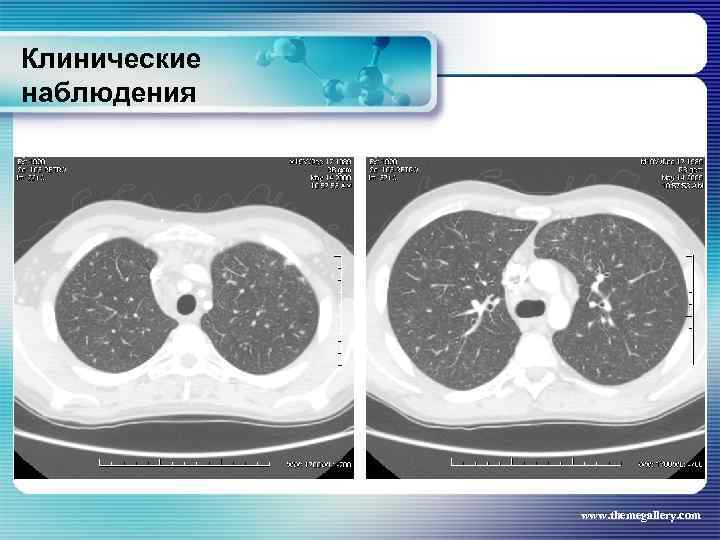

Клинические наблюдения Больной Ф. , 27 лет Заболел с начала сентября 2009 года, когда появилось повышение температуры до 38°С, похудание (за 2 недели похудел на 5 кг), профузная ночная потливость, болевые ощущения в грудной клетке. При рентгенограмме органов грудной полости – расширение тени средостения в обе стороны, в в переднем средостении образование мягкотканной плотности с полициклическими контурами. При лабораторном обследовании выраженные признаки биологической активности. Выполнена СКТ www. themegallery. com

Клинические наблюдения Больной Ф. , 27 лет Заболел с начала сентября 2009 года, когда появилось повышение температуры до 38°С, похудание (за 2 недели похудел на 5 кг), профузная ночная потливость, болевые ощущения в грудной клетке. При рентгенограмме органов грудной полости – расширение тени средостения в обе стороны, в в переднем средостении образование мягкотканной плотности с полициклическими контурами. При лабораторном обследовании выраженные признаки биологической активности. Выполнена СКТ www. themegallery. com